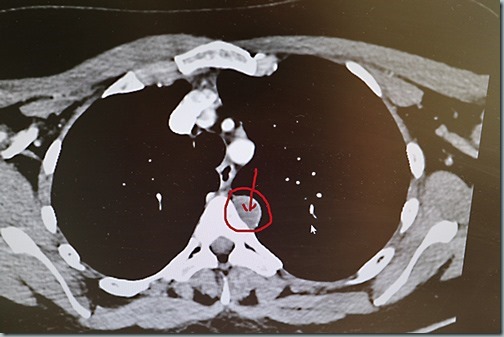

Muss sich mein Körper gedacht haben. Die Lymphknoten am Schulterblatt sind harmlos und unauffällig, aber als Zufallsbefund wurde “subpleural im Oberlappen links eine 14×22 mm messende Läsion” gefunden. Differentialdiagnostisch ist ein Schwannom (was für ein Wort) von BWK 4 zu denken und ein MRT der BWS wird empfohlen. Na denn. Termin hab ich in 4,5 Wochen, in Varel haben sie mir schon vor der Frage was denn gemacht werden muss gesagt, das sie im August sind terminlich.

Heute gelernt: da MRT- und CT-Bilder von unten aufgenommen werden, ist links rechts und rechts links. Hier also: Läsion an BWK 4 auf meiner linken Seite, die da eindeutig nicht hin gehört.